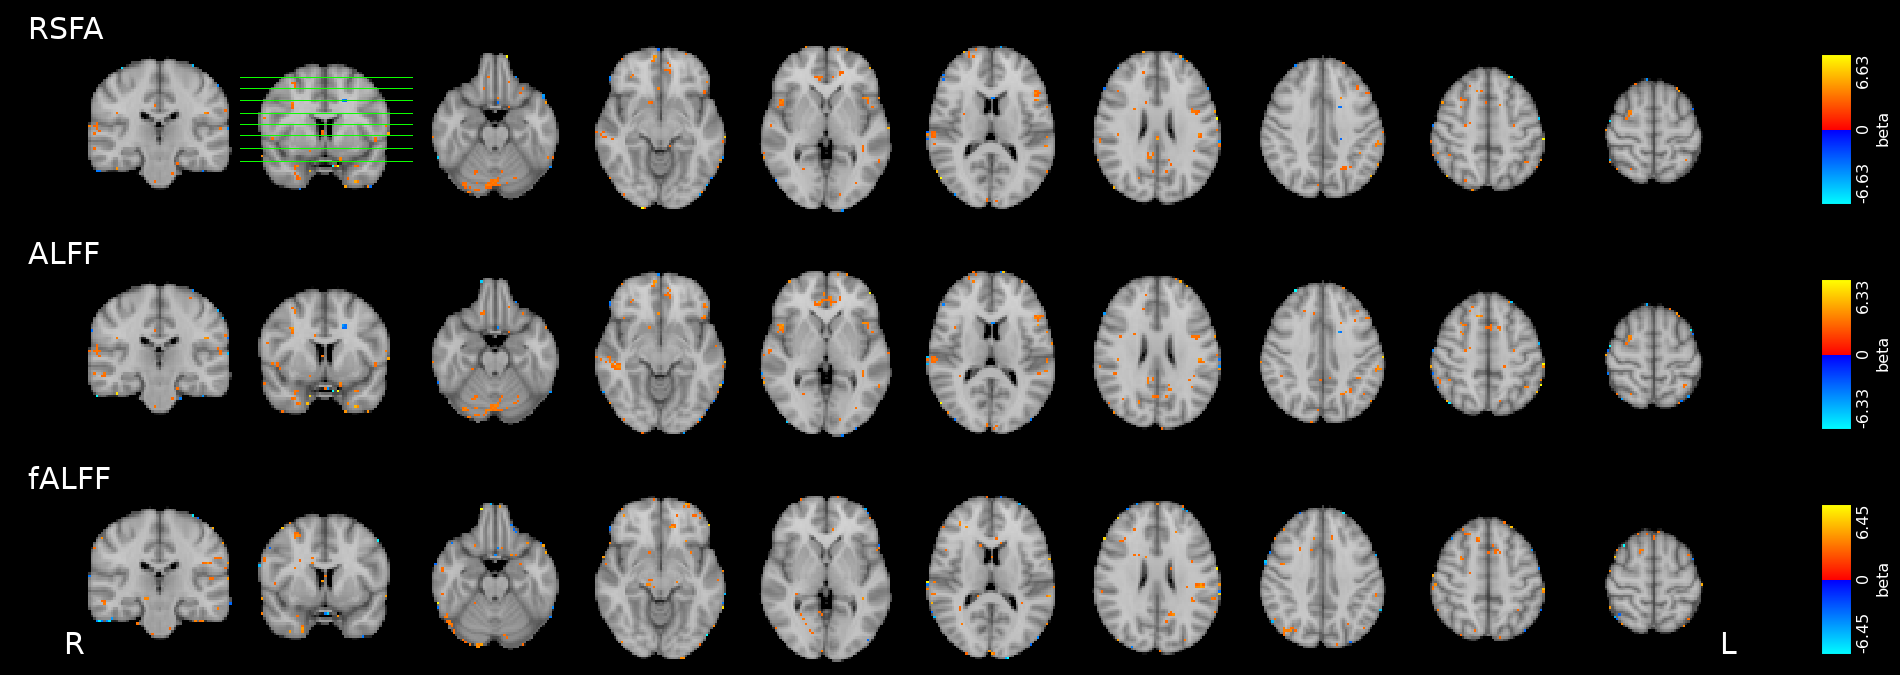

Results: CVR and RSF

Physiology and RSF

We used 3dLMEr¹ to set up the following LME models (R syntax):

Effect of Sex

Only sex had a significant effect on RSF

Effect on CVR

Results: CVR and RSF

Golestani et al. 2016 (NeuroImage)